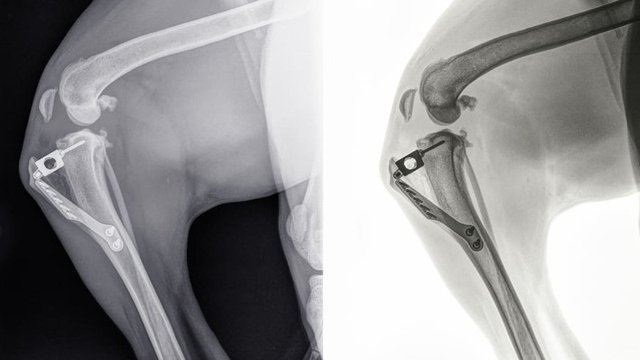

Como pruebas de diagnóstico por imagen utilizamos la radiografía para evaluar la osteoartrosis, confirmar una patología de rodilla y descartar otras enfermedades.

Para los casos de rotura de ligamento cruzado craneal tanto si es total como parcial siempre es recomendable una intervención quirúrgica. Los procedimientos que se utilizan más frecuentemente consisten en una osteotomía de la tibia, lo que supone realizar un corte en la misma para disminuir el ángulo de la meseta tibial, que posteriormente se estabiliza con una placa metálica. Dentro de estas técnicas utilizamos la osteotomía en cuña de la tibia craneal (CTWO) que consiste en retirar un fragmento de hueso en forma de cuña; y la osteotomía de nivelación de la meseta tibial (TPLO) en la que realizamos un corte en la tibia de forma semicircular y rotamos la meseta tibial hasta el ángulo deseado.